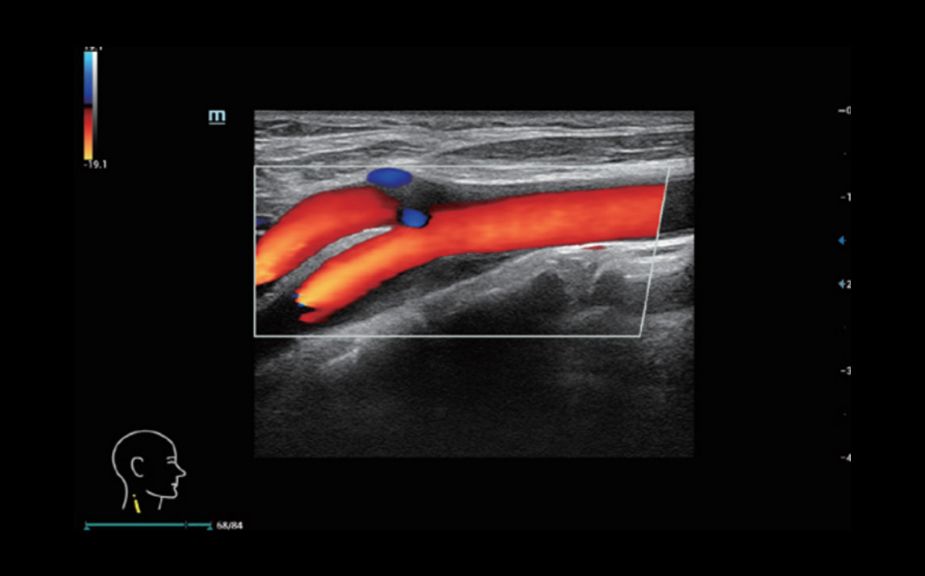

Новейший подход к изучению сосудистой гемодинамики: V Flow

Используются маркированные цветом вектора для индикации значения скорости и направления движения клеток крови. Благодаря сверхвысокой частоте кадров V Flow обеспечивает чрезвычайно четкую, точную и независимую от угла комплексную оценку сосудистой гемодинамики с возможностью всестороннего анализа.

V Flow

Новейший подход к изучению сосудистой гемодинамики: V Flow

Используются маркированные цветом вектора для индикации значения скорости и направления движения клеток крови. Благодаря сверхвысокой частоте кадров V Flow обеспечивает чрезвычайно четкую, точную и независимую от угла комплексную оценку сосудистой гемодинамики с возможностью всестороннего анализа.

V Flow